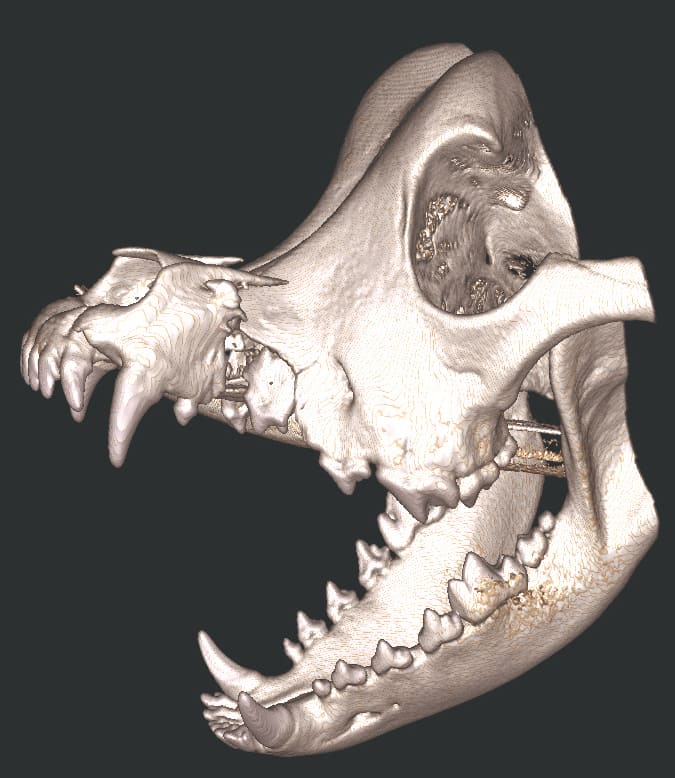

Repair of Maxillofacial Fracture

Pets can be involved in trauma that can cause fractures to their head, teeth, and jaw bones. Correctly repairing these fractures is extremely important for your pet to have normal function of their mouth. If a jaw fracture is allowed to heal in an abnormal position, your pet may have great difficulty chewing and can be in significant pain. Many fractures can be successfully treated with minimally invasive oral procedures, but more complicated cases may require bone plating techniques. The Center offers cone beam CT imaging which provides extremely detailed images of the bones of the head and skull. Advanced imaging with CBCT facilitates selection of the best surgical technique to get your pet back to eating and comfort as soon as possible.